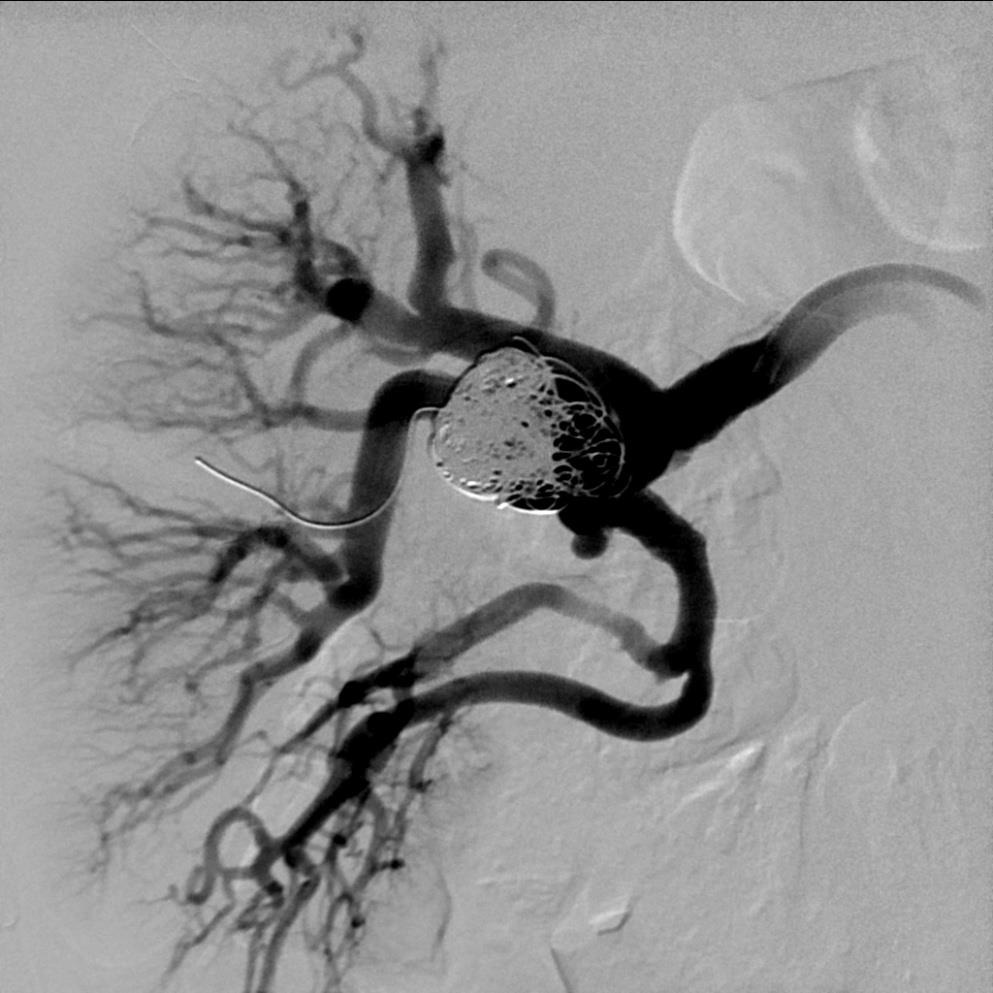

微导管经支撑架网眼进入动脉瘤内

微弹簧栓子栓塞动脉瘤后造影显示,动脉瘤完全填塞,右上极肾动脉开放,实质染色没有充盈缺损。